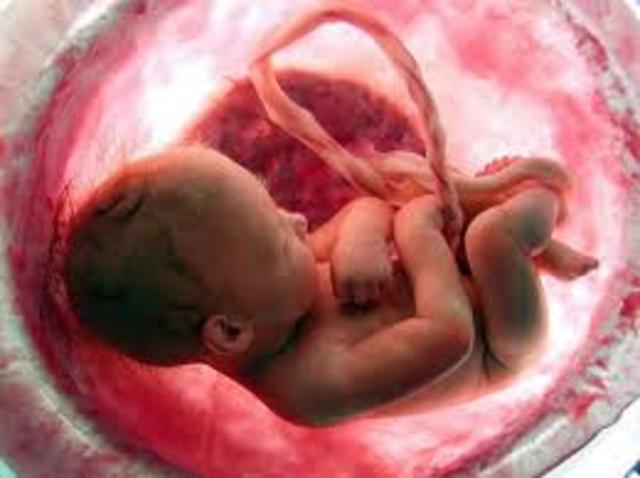

• Fetal

Fetal

Se comprende desde el tercer mes hasta el nacimiento. El embrion casi adquiere su forma casi definida. El embrión se llama feto.

• 12° Tercer mes

12° Tercer mes

El feto mide 3 cm pesa enttre 15 y 20 gramos,

.Comiena a esbosearse kas uñas, ek refkejo de succion